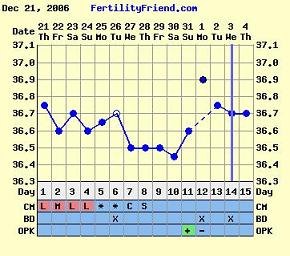

Bettike! Köszi a táblát, abból tudtam meg, hogy hányadik napon vagyok